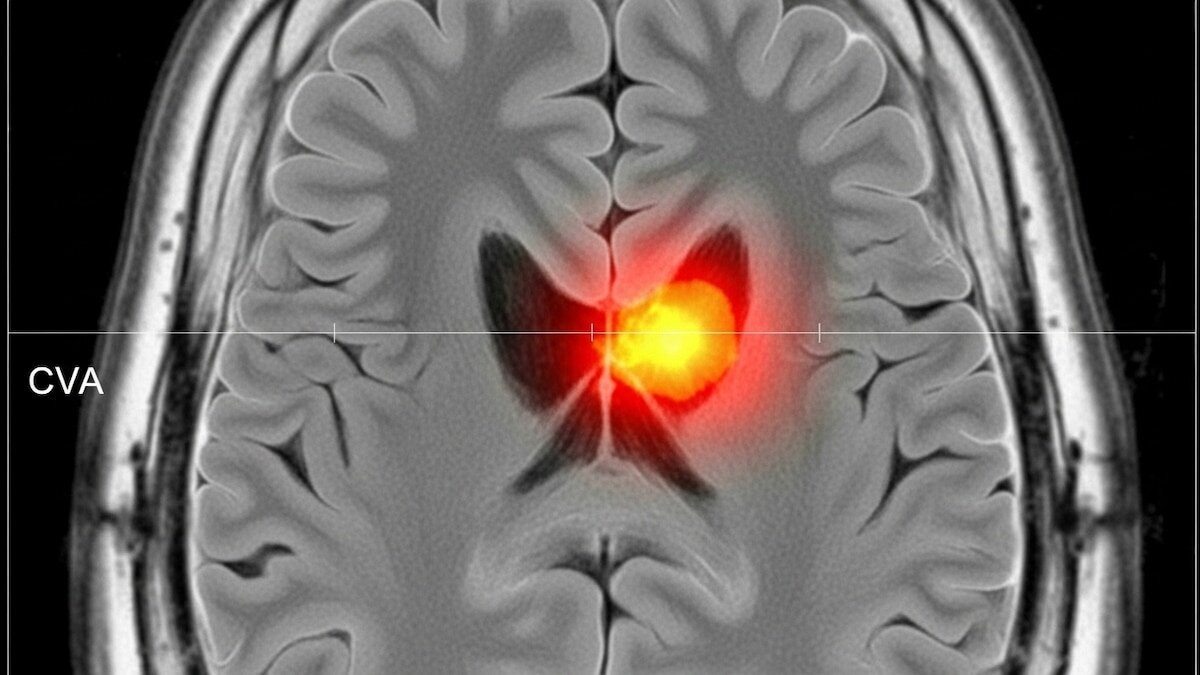

Accidentes cerebrovasculares: el 90% se puede evitar con hábitos saludables

Los accidentes cerebrovasculares (ACV) se encuentran entre las principales causas de muerte y discapacidad en el mundo. Las proyecciones internacionales alertan que, si no se fortalecen las medidas de prevención y control de los factores de riesgo, los casos seguirán aumentando de manera sostenida en las próximas décadas.